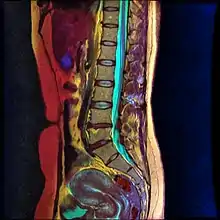

Magnetic Resonance Image of Lumbar Spine courtesy of Nevit Dilmen

Lumbar sympathetic neurolysis is performed between the L1-L4 vertebrae with separate injections at each vertebra junction. The chemicals used for neurolysis of the nerves cause destructive fibrosis and cause a disruption of the sympathetic ganglia. The vasomotor tone is decreased in the area affected by the neurolysis, which in addition to arteriovenous shunting, create a light pink appearance within the affected area. Lumbar sympathetic neurolysis alters the ischemic rest pain transmission by changing norepinephrine and catecholamine levels or by disturbing afferent fibers. This procedure is mainly used only when other feasible approaches to pain management are unable to be used.[6]